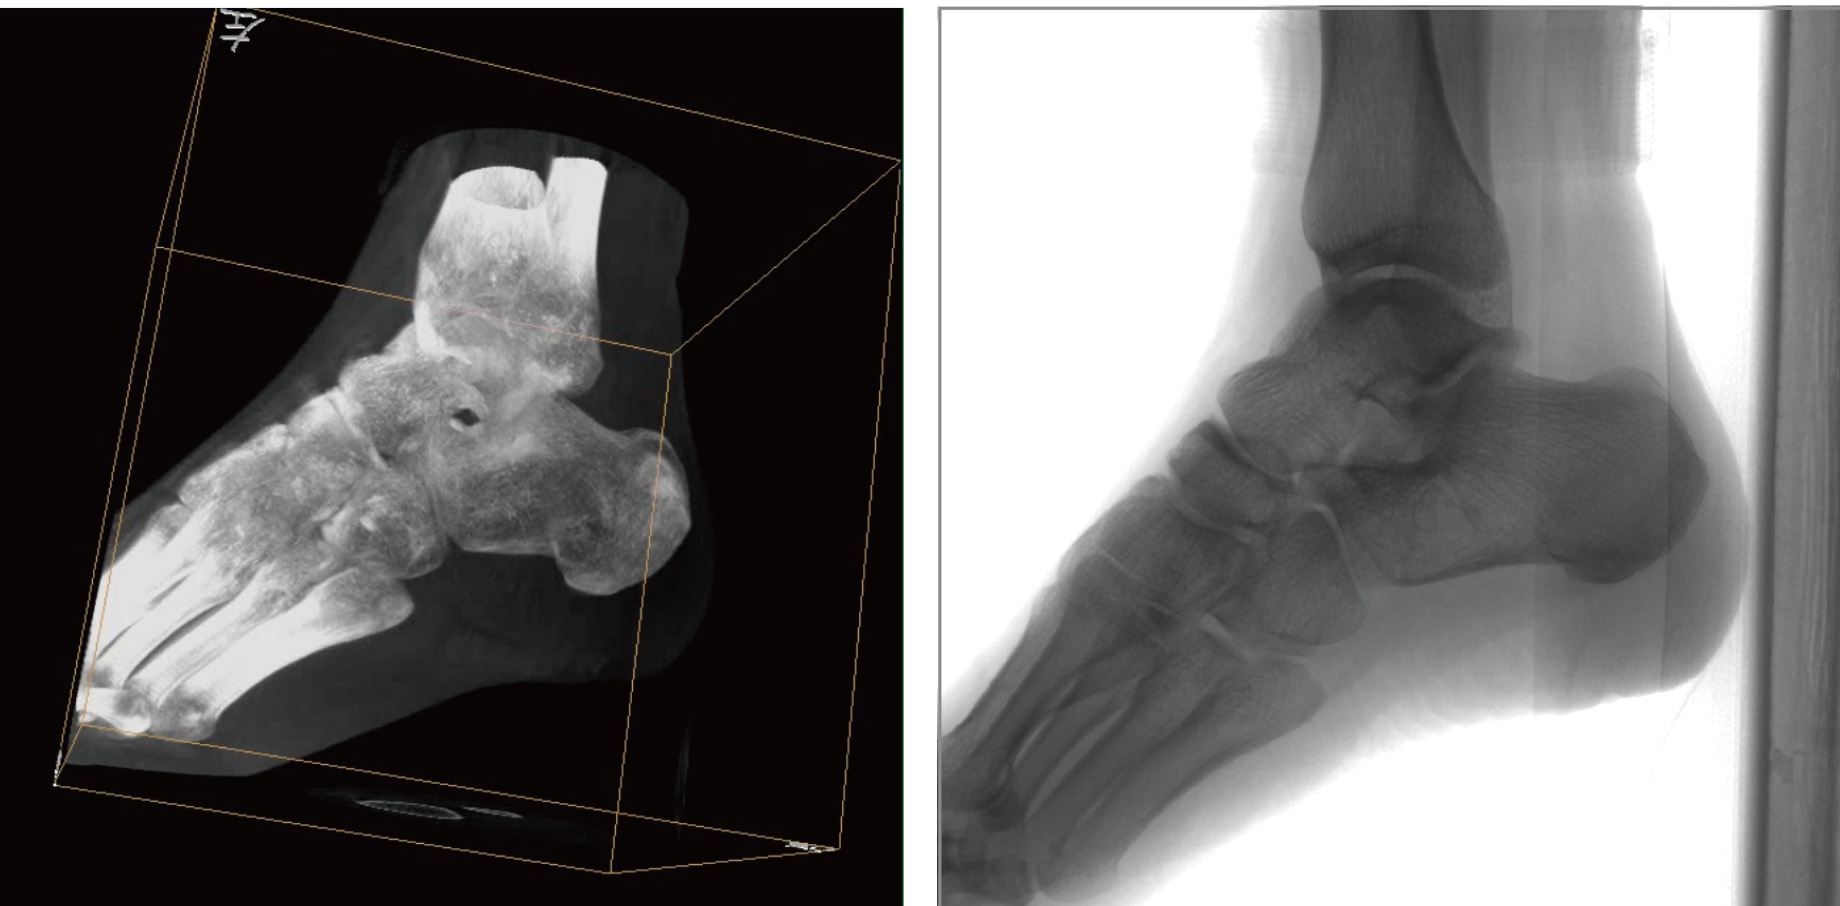

普爱医疗天弓PLX7500骨科三维C形臂,作为“术中CT”,在手术中快速生成类CT断层图像和立体三维图像,为医者提供更全面的图像信息,能够准确地观察植入物的情况,例如螺钉内固定术入钉的位置和角度。天弓PLX7500三维C形臂性能特点:

PLX7500骨科三维C形臂通过采集,能在术中快速地生成横断面、矢状面、冠状面和可旋转的立体图像,给术者提供360°无死角的观察角度,准确判断骨组织和植入物的情况,为手术的实施提供保障,极大提高手术成功率,减少并发症概率。

超大区域,超高像素。术中三维成像区域可达直径Φ18cm,高18cm的圆柱形区域,各个维度均为400立体像素,画质细腻清晰。